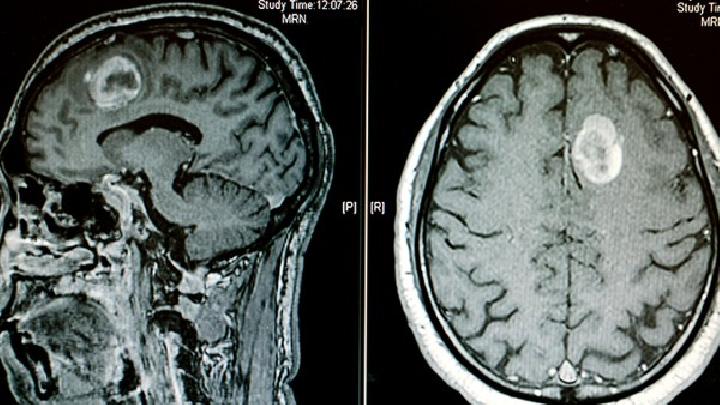

少女先天性脑瘫发病原因主要有以下几点:①胎儿脑缺氧,生产时间长以及产前利用镇痛剂、平静剂皆可克制胎儿呼吸,造成气体互换停滞、脐带绕颈、胎盘早剥、前置胎盘,皆可致胎儿脑缺氧。此类患儿约百分之三十有复生儿窒息的病史②脑出血,产伤、急产、难产、出血性疾病皆可致颅内出血此类患儿约百分之十五在复生儿期即有惊厥发作。③胚胎期脑发育非常,如小脑畸形、天赋性脑积水或无大脑等天赋性畸形④母亲怀胎时期受外伤或患重症熏染、怀胎毒血症、糖尿病以及放射性照射皆可影响胎儿脑发育而致永世性脑陵犯。⑤母亲怀胎早期患风疹、带状疱疹、巨细胞包涵体病、弓形体病等均可使胎儿中枢神经体系遭受陵犯而发病;④早产儿⑥逾期产儿,胎盘变性坏去世,与早产儿同样可引起低氧血症致胎儿脑缺氧。⑦遗传基因缺陷,家属或嫡系家属中有天赋性遗传疾病。⑧其他,吸咽、沈酒、血虚、长期服药等。⑨脑膜炎、脑炎或周身重症熏染所致的脑病,头部外伤所致的颅内出血,一氧化碳中毒等疾患。其次为重度营养不良、重度脱水并发脑静脉血栓形成等。此类病因多明确,亦可诊为某病的后遗症。